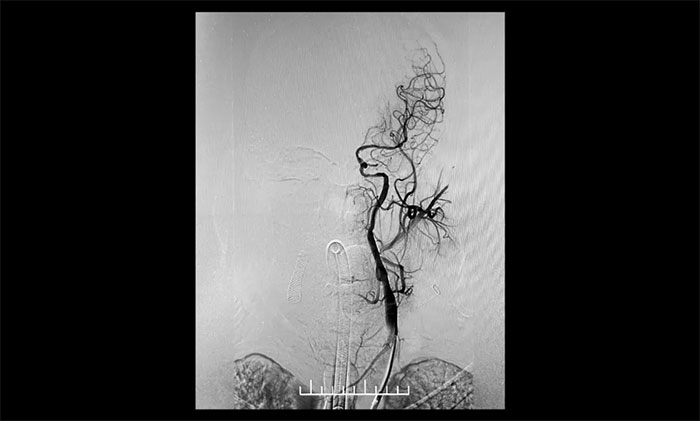

经微导丝成功进入狭窄、闭塞颈内动脉,在支架保护下,进行球囊逐段扩张,支架置入……,经多次球囊扩张,置入支架后,造影显示左颈内动脉起始段狭窄明显改善,左颈内动脉颅内段顺利再通,左颈内动脉眼动脉段、后交通段狭窄明显改善。造影及3D造影见左颈总动脉、左颈内动脉、左大脑中动脉显影可,行支架CT见颅内支架成形可,手术取得成功!

▲术后,左颈内动脉起始段狭窄明显改善,左颈内动脉颅内段顺利再通,左颈内动脉眼动脉段、后交通段狭窄明显改善